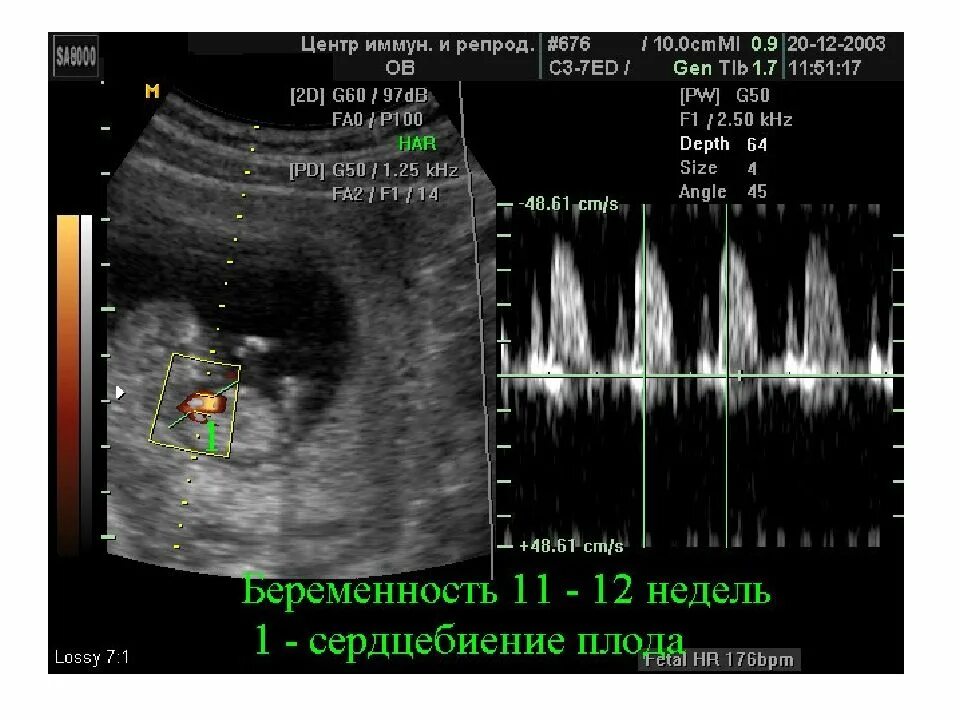

На какой недели бьется сердце плода